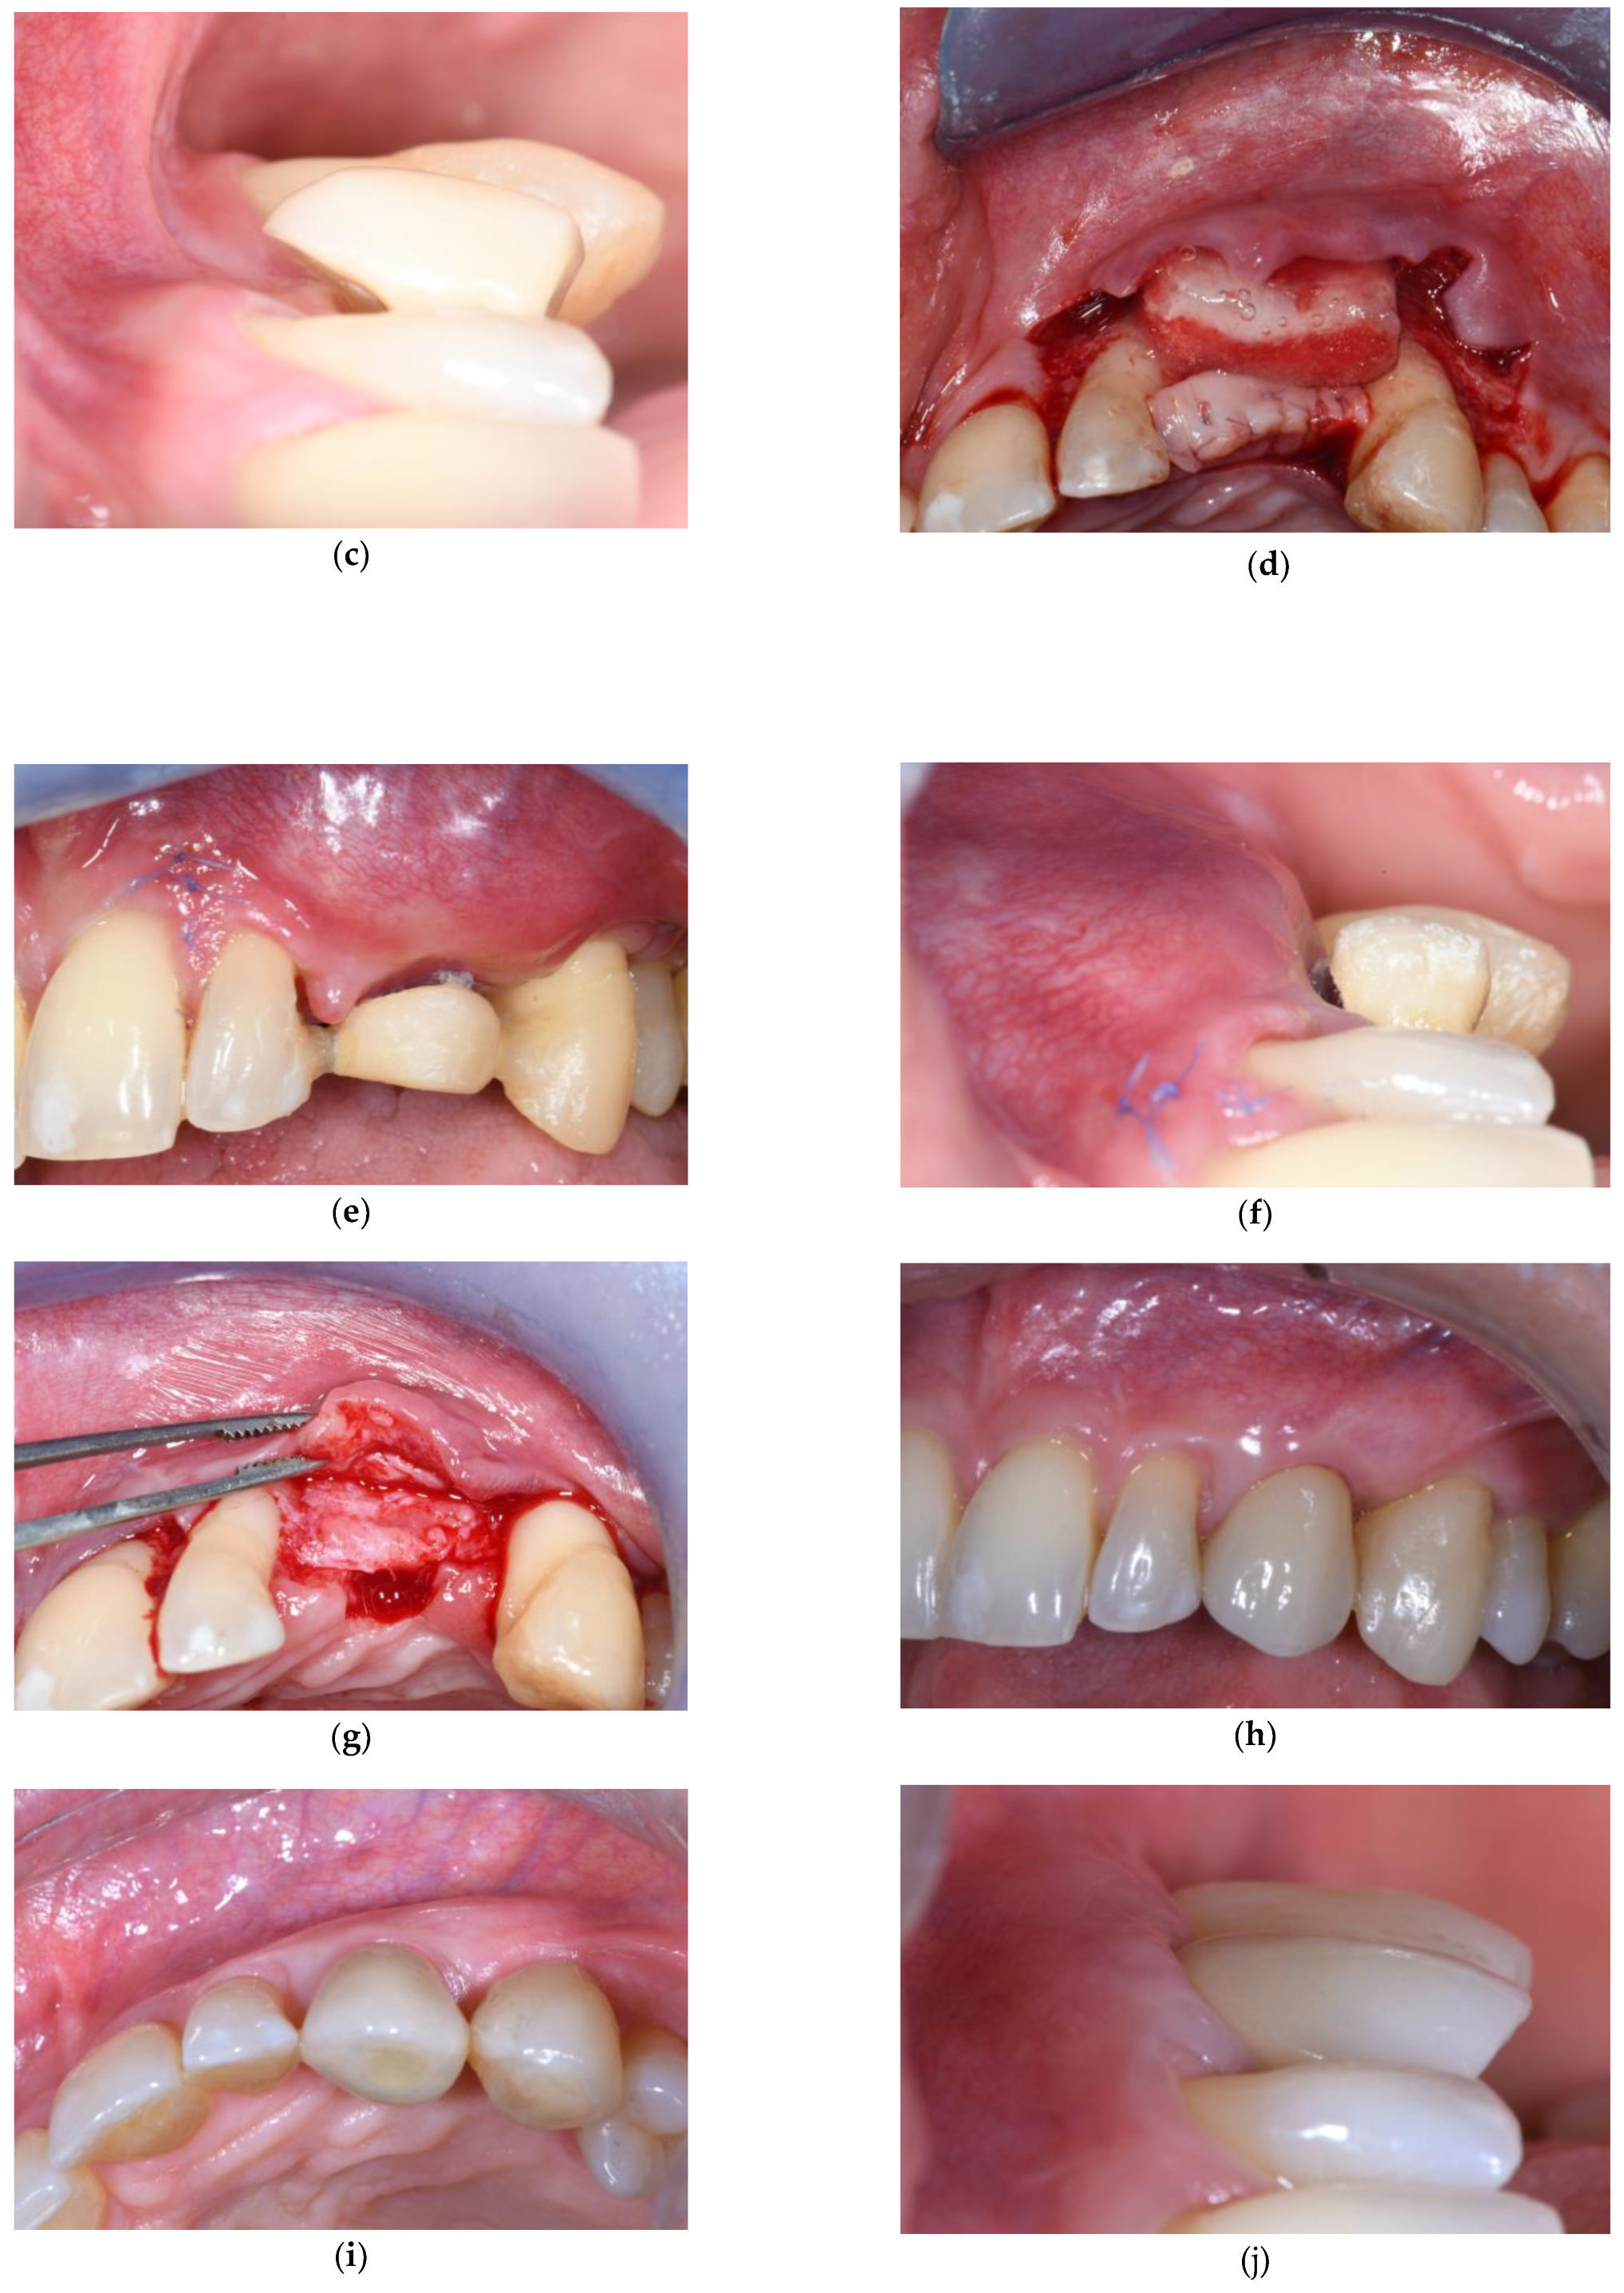

2. Connective Tissue Substitutes: Properties and Applications

3.2. Soft Tissue Augmentation During Implant Installation

3.3. Soft Tissue Augmentation After Implant Installation